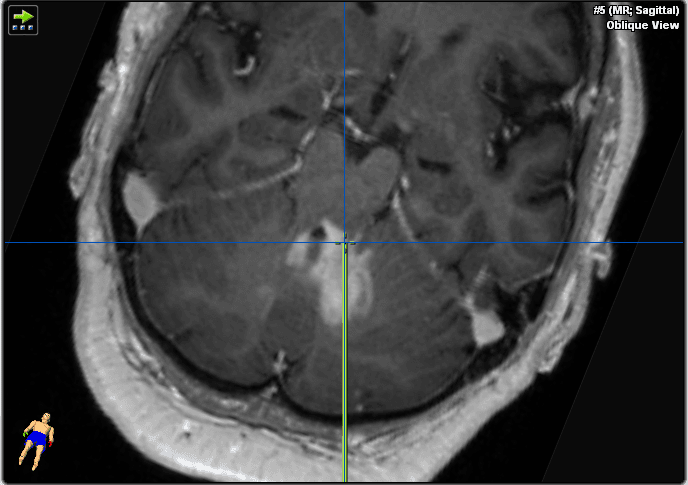

Abbiamo deciso di eseguire una biopsia cerebrale invece di un intervento chirurgico transcorticale aperto per testare la presenza di linfoma, per le ragioni esposte nella sezione sopra (Figura 3). La precisione del sistema di neuronavigazione è più precisa in posizione supina rispetto a quella prona grazie alla migliore visibilità del volto e della superficie convessità per la telecamera di navigazione. Abbiamo quindi optato per la posizione supina per consentire la massima precisione spaziale in questa procedura. La biopsia stereotattica sarebbe tecnicamente più difficile a causa della procedura basata sul telaio, che richiederebbe una posizione semi-seduta e un maggiore rischio di embolia atmosferica. Nelle lesioni puramente del tronco encefalico, la biopsia stereotattica basata su ronger sarebbe la tecnica più favorevole, causando meno traumi tissutali (ago biopsico più piccolo, ma anche minore volume di campioni). Il pavimento del quarto ventricolo deve essere evitato nelle procedure chirurgiche a causa del suo ruolo critico nella funzione del tronco encefalico.

Figura 3. Queste immagini mostrano il piano della traiettoria.